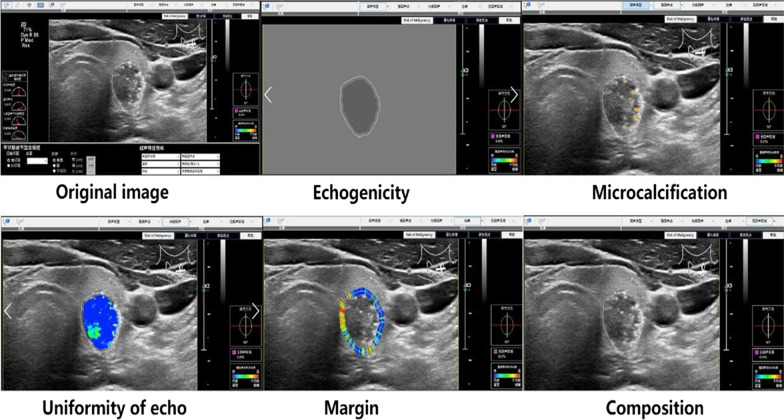

A physician more than 5-year experiences in ultrasound diagnosis marked the anteroposterior diameter and transverse diameter of the original standard images of 296 thyroid nodules with the cursor. Patient data and characteristics were blinded in AmCAD-UT application. Then the computer automatically traced the initial contour of ROI, identified the ultrasound image features of the thyroid nodules, then labeled and quantified the features in different colors, including echo type of the nodules, solid/cystic nature, uniformity of echo, nodular morphology, aspect ratio, and with or without microcalcification (Figs. 1, 2). Finally, the CAD system automatically generated the malignancy risk assessment report and suggestions of thyroid nodules based on 2015 ATA Guidelines [5], 2017 ACR TI-RADS Guidelines [8], 2016 AACE/ACE/AME Guidelines [18] and 2011 Kwak TI-RADS Guidelines [19] in the program.

Fig. 1.

Automatic identification and quantization of ultrasound features of malignant thyroid nodules by the Am CAD-UT Detection System